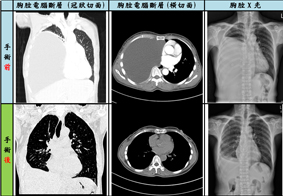

比較圖_手術前後

經本院胸腔內科王秉槐主任,仔細詢問病史及診斷,發現病人胸腔內的陰影有比過去的胸腔影像擴大的現象,幾乎占據右胸的八成空間,懷疑是一個大約21x16x14 cm的巨大囊腫,從縱膈腔往右側胸腔壓迫,將右側肺部壓迫到剩不到兩成的肺功能,並導致心臟被嚴重推擠。

後由胸腔外科劉昭宇醫師詳細說明手術治療相關建議,病人於今年一月初接受胸腔微創手術治療,將與病人共處多年的縱膈腔囊狀畸胎瘤取出,使其被瘤壓迫多年的右肺重新恢復功能,術後迄今恢復良好,多年來的不適症狀獲得解除,肺功能恢復正常。

本案例係因腫瘤影像之表現特殊,以純水囊狀來呈現,即使經多年來數次就醫,仍長久以來被認為是慢性膿胸、肋膜積水等等病因來治療,以致無法獲得正確之治療。縱膈腔腫瘤的治療以外科手術為主,傳統開胸手術包含正中胸骨切開或側後胸切開術,但近年來因微創胸腔鏡手術發展,我們僅用一個4公分之側胸切口及一個1公分的引流管傷口,便將其巨大囊腫取出,病患術後恢復良好迅速,且將來無復發之可能。